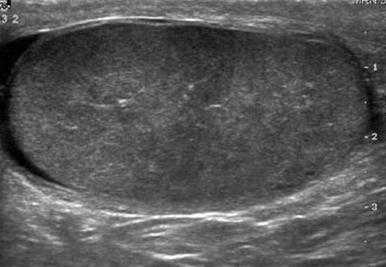

В норме яичко определяется как гомогенная структура овальной формы, эхогенность которой сравнима с эхогенностью щитовидной железы.

На первой картинке визуализируется гомогенная структура яичка в продольной плоскости. Текстура яичка такая же, как у щитовидной железы, представленной на втором изображении.

Белочная оболочка яичка на УЗИ представляет собой плотную полоску вокруг яичка. Яичко окружено влагалищной оболочкой, на УЗИ выглядящей как гипоэхогенное кольцо вокруг яичка. Висцеральная пластинка влагалищной оболочки прилежит к яичку и отделена от париетального листка тонким слоем серозной жидкости.

На данном изображении представлен срез яичка в поперечной плоскости. Яичко визуализируется как гомогенное образование, окруженное гипоэхогенным кольцом фиброзной ткани. Это кольцо является влагалищной оболочкой, содержащей между своими листками небольшое количество жидкости.